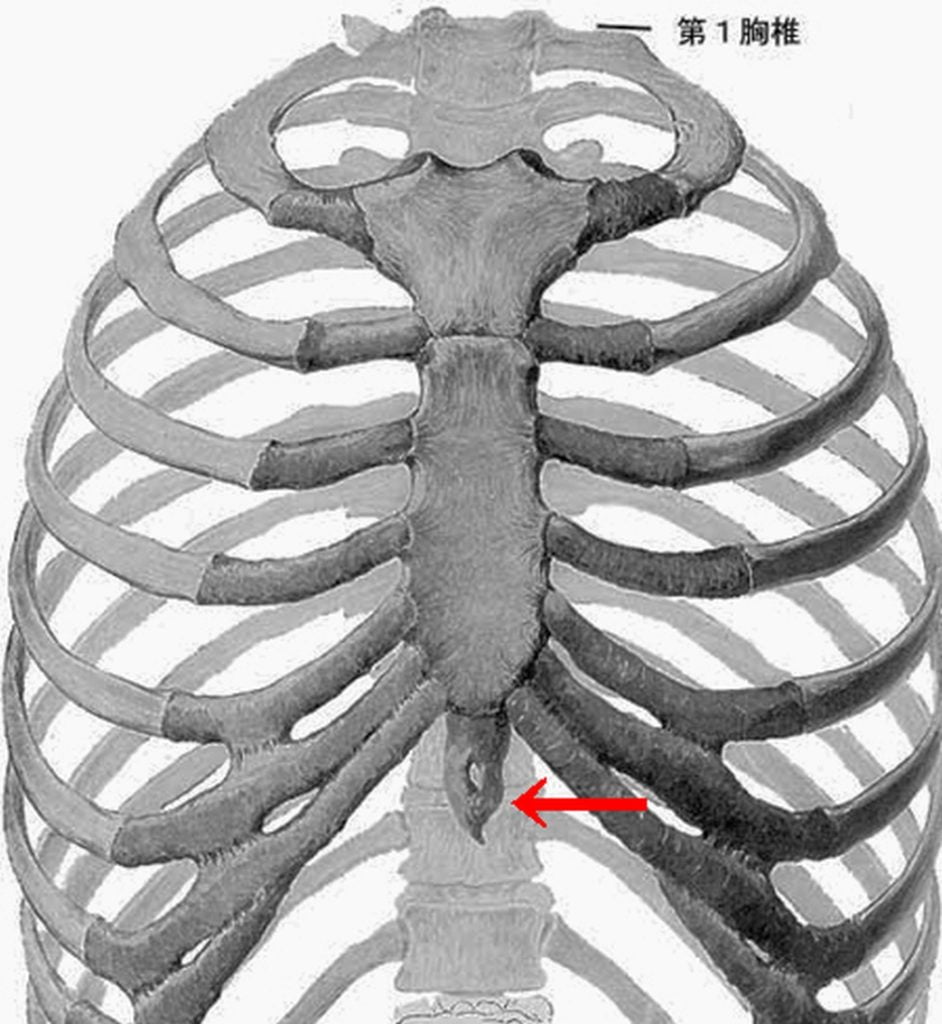

両肘は"丹田"部より上,胸の下X線上にクロスした状態で咄嗟に

↓下図は大変恐縮ですが,間違いがあります。 相手 人形の"2発目の手”は右手となります。

左手からではなく【正】は相手の右手からです。

私のX線上の"受け"の下の肘に当たり,

相手からの下からのスィング打撃は,日本の伝統空手の典型的なクロス="十字受け"となり

心臓の上部の肋骨にヒビが入っているのか?

それとも今回とは無縁の内蔵疾患に依る"狭心症"か何かだろうか?

何処か肋骨にヒビが入っているかも知れない。心臓部を直撃(打たれた)された可能性がある。

分析出来る事は,相手の肋骨の直下,つまり,みぞおちの上の骨,

"剣状突起部位"と自分の"ひざの皿"が当たったのではと推測しています。

相手の”浮遊肋骨"部=肋骨の最下部

と自分の膝が当たった可能性も否定は出来ない。

"浮遊肋骨"という左右2対の肋骨の場所は

胸骨に接しずに浮いているため,

強い外力が及ぶと"折れやすい"のです。